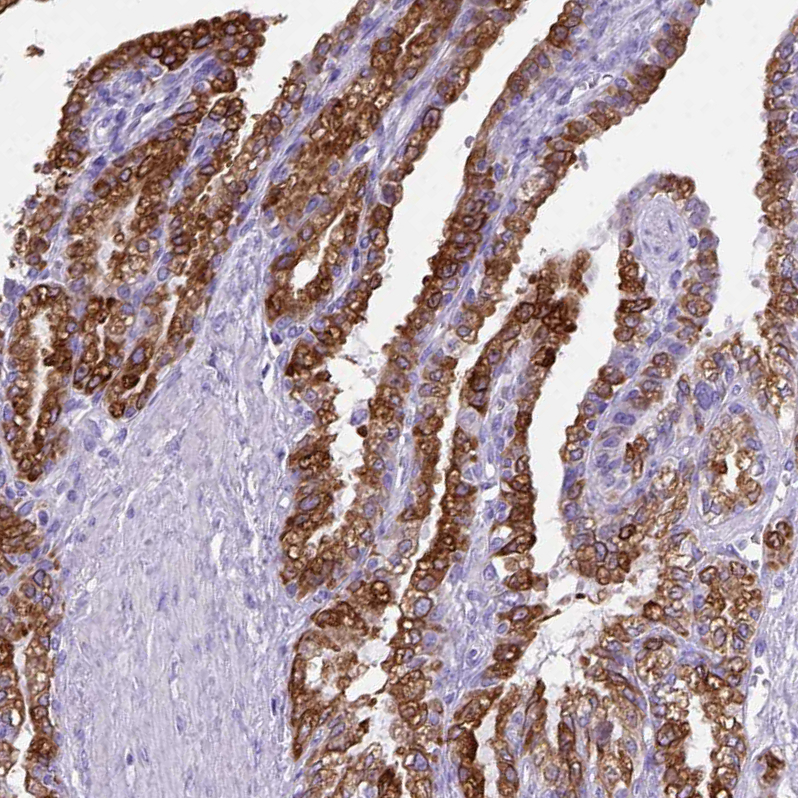

Immunohistochemistry analysis in human seminal vesicle and pancreas tissues using HPA045064 antibody. Corresponding PTGES RNA-seq data are presented for the same tissues.